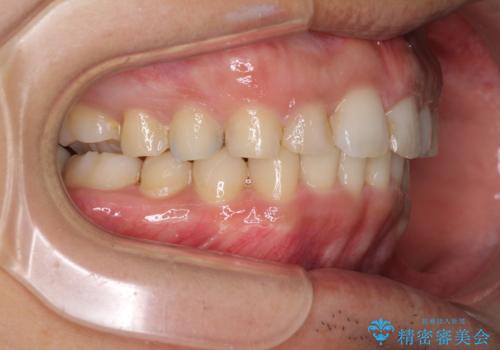

- 深い咬み合わせと前歯のデコボコ、奥歯の欠損を気にして来院された患者様です。

歯列矯正はインビザラインを使用し、矯正治療中の適切な時期に奥歯の欠損部位にインプラントを埋入することとしました。